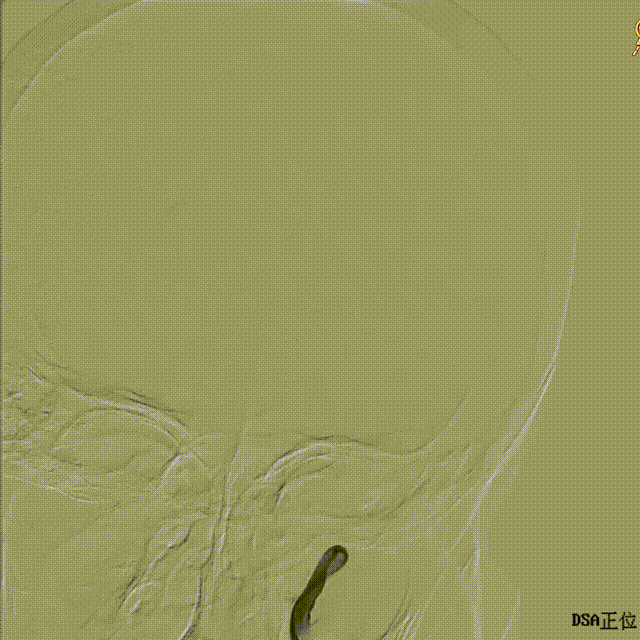

术后正侧位造影

正位

侧位